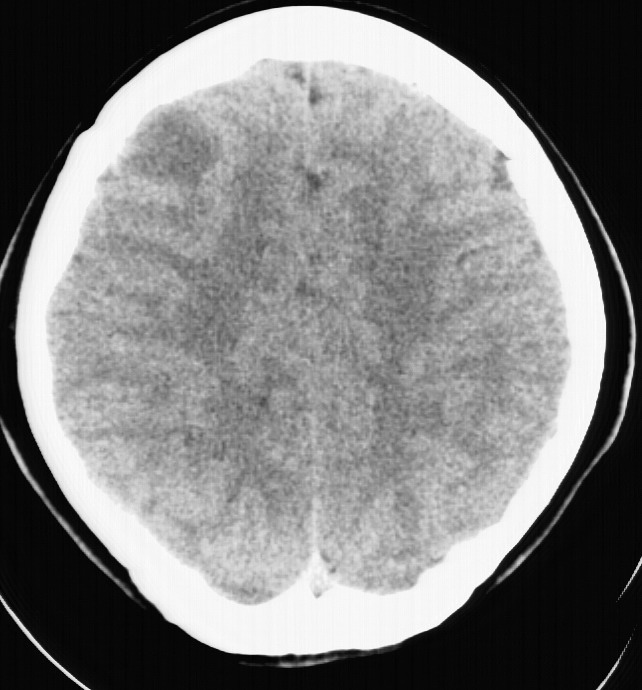

标题: CT5853:右额叶上部占位请会诊

女,34岁,自述头晕胀2年,近期感精神恍惚,无发热,实验室检查阴性。

右顶叶靠近脑表面圆形低密度灶,周围无水肿及占位效应,增强病灶无明显强化,考虑:右顶叶低分级星型细胞瘤。

右额叶上部皮质区见类圆形低密度区,边界不清,无强化,无钙化。

支持大多数战友的意见,1级星形细胞瘤。